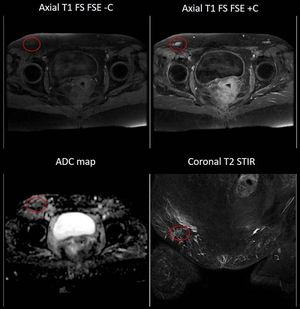

High-resolution, multiparametric (morphological and functional) MR Imaging of the pelvis. Figure illustrates a pelvic lymph node metastasis (red circle), characterized by hypercellularity (low ADC) and Gd uptake.